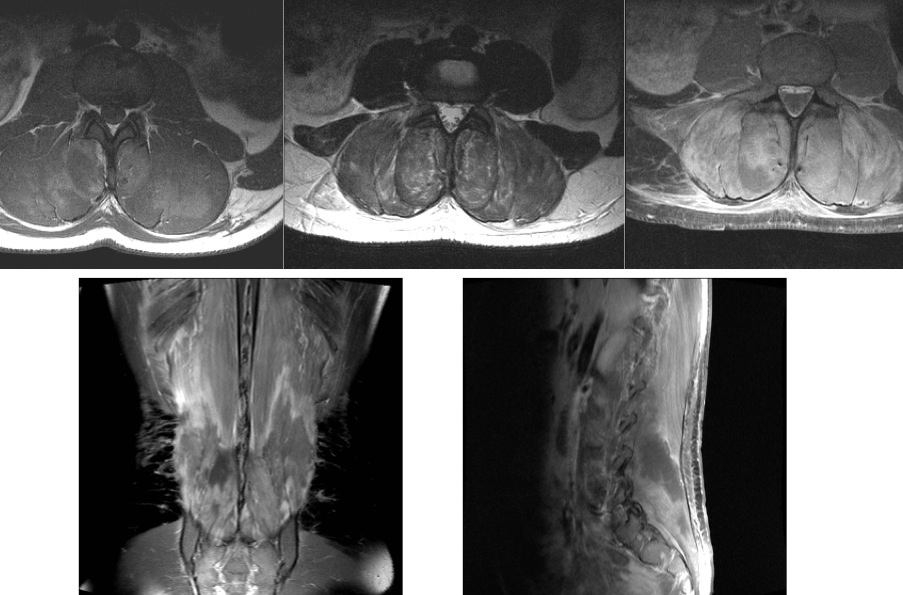

Acute bilateral paraspinal compartment syndrome

Patient is a bit of a gym junkie and did a particularly strenuous session prior to the onset of symptoms. Patient had hematuria with 2 days of severe low back pain radiating into the groin and right leg. Khan et al. Acute paraspinal compartment syndrome. A case report. J Bone Joint Surg Am. 2005 May; 87(5):1126-8.

Courtesy Bill Breidahl, MD

Courtesy Bill Breidahl, MD